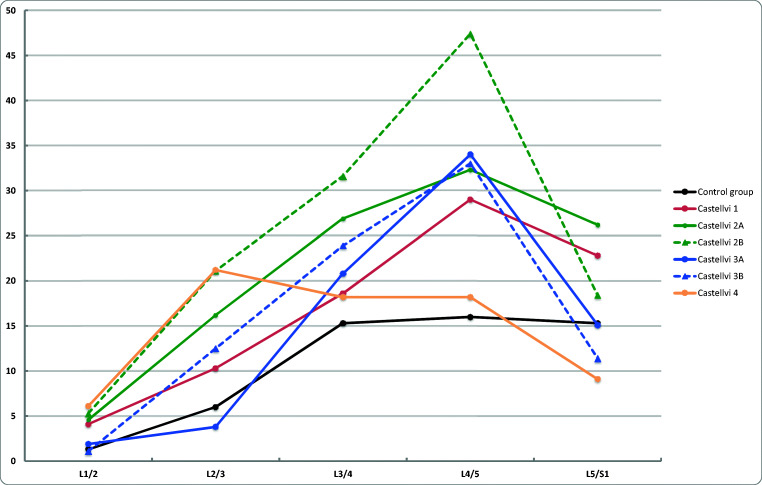

The prevalence of DD in Castellvi groups and in the control group by disc level is shown in Fig. 2. After adjustments with age and sex, the prevalence of DD was significantly higher in Castellvi type II group than in the control group at lumbar levels L1/2, L3/4, and L4/5 (Table 1). With regard to type III, the prevalence of DD was higher at lumbar levels L3/4 and L4/5 than in the control group. In addition, the prevalence of DD was significantly higher at L1/2 and L4/5 in type IV group than in the control group. At L5/S1, the prevalence of DD was higher in the control group than in type II, III, or IV groups. When analyzing type I and control groups, the prevalence of DD was significantly higher in type I group only at L2/3. After combining Castellvi types II, III, and IV into one pooled group, significant differences were found at all lumbar levels except L2/3. Table 1 summarizes the distribution of disc degeneration by lumbar level in different Castellvi groups and controls. Figure 3 demonstrates an example of type IV LSTV with general lumbar degenerative changes and a control subject with less degeneration.

Fig. 2.

The prevalence of disc degeneration (in percentage) by disc levels in Castellvi groups and the control group

The prevalence of FD in Castellvi groups and in the control group by disc level is shown in Fig. 4. After adjustments with age and sex, the prevalence of FD was significantly higher at L4/5 in Castellvi groups I, II, and III than in the control group. In type II group, the prevalence of FD was additionally significantly higher at L2/3 and L3/4 than in the control group. In type IV group, the prevalence of FD was higher at level L2/3 than in the control group. Again, when Castellvi types II, III, and IV were combined into one pooled group, significant differences were found at lumbar levels L2/3, L3/4, and L4/5 (Table 2).

Fig. 4.

The prevalence of facet degeneration (in percentage) by disc levels in Castellvi groups and the control group

Studies have usually evaluated the association of LSTV with degenerative changes only at the transitional and adjacent levels, showing accelerated degeneration at the level above and protective effect to the transitional level [11, 14, 20]. The rationale for this is that when one segment is stabilized, the other segment will have greater mobility and stress further leading to accelerated degeneration [20]. This is a similar phenomenon to lumbar stabilization studies where fusion has been associated with accelerated disc degeneration adjacent to fusion level [24, 25]. However, as all lumbar segments contribute to movements of the lumbar spine [26], in the authors’ opinion it is of interest to also assess the other lumbar segments than only the transitional and adjacent levels. In fact, we found LSTV and especially type II Castellvi group to have significantly greater degenerative changes also at the upper lumbar levels than the control group (Fig. 2, Fig. 3). Therefore, we suggest to consider also the upper lumbar levels when evaluating the patient’s clinical status and to assess these levels in the studies where one segment is stabilized.